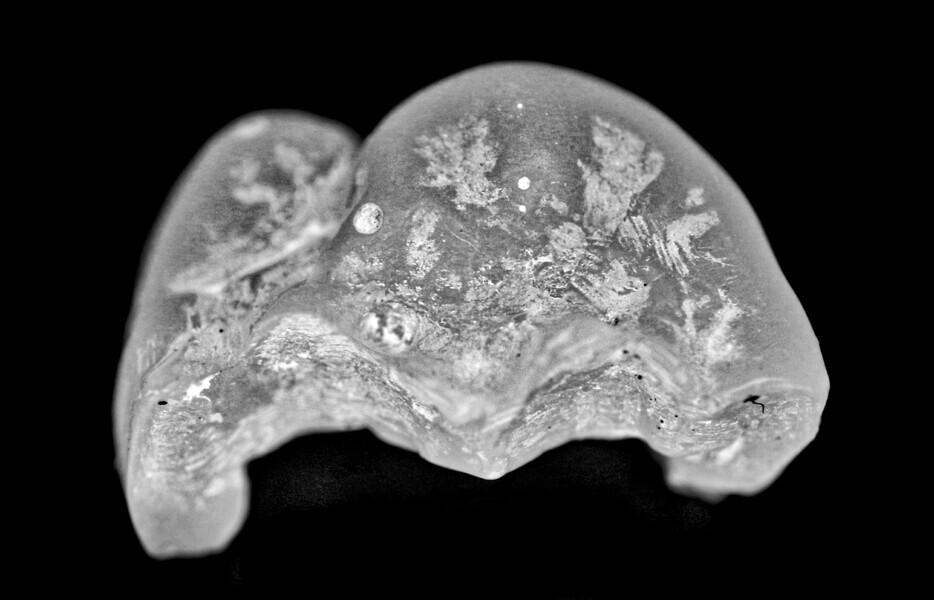

Fig. 12: Zirconia onlay.

This study investigated cobalt–chromium indirect restorations, but other metal powders currently used in additive manufacturing, including stainless steel and titanium, could be employed.7 In addition, the novel workflow could be applied to non-metal, aesthetic materials such as zirconia and lithium disilicate. The use of zirconia was also explored in this investigation with a single unit, using the same workflow, and achieved similar results but with milling rather than additive manufacturing (Figs. 12 & 13).